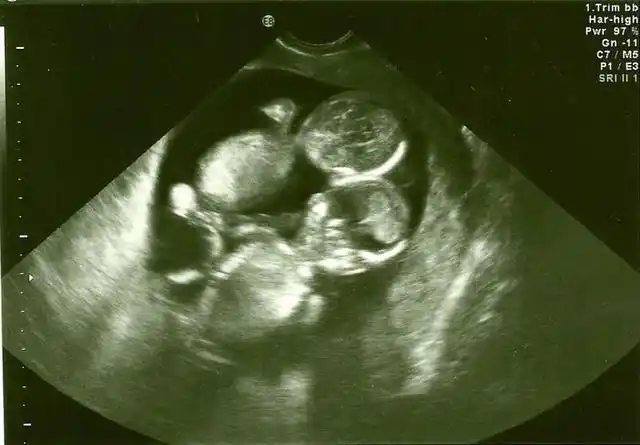

双胞胎宝宝今天的b超终于知道真相了

双胞胎移植40天

同卵双胞胎b超图